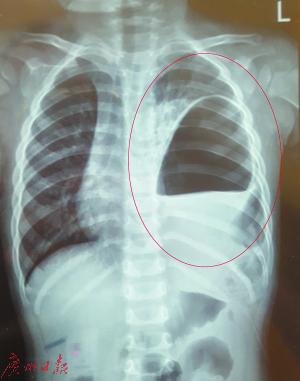

东莞一男童腹痛入院后发现膈肌有洞 脾胃跑到胸腔中

示意图5:腹腔脏器疝入胸腔